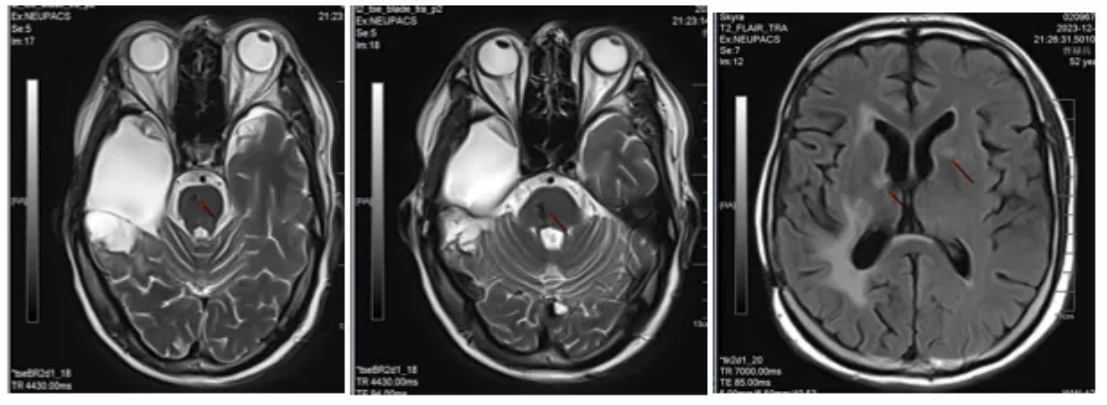

2023-12-29脑部MRI随访复查:右侧颞叶胶质瘤术后;右侧基底节区后部点状异常信号,较前(2023-09-22)相仿,建议定期复查;右侧大脑脚华勒氏变性;桥脑小片状异常信号,较前增大,软化灶并含铁血黄素沉积?转移待排;右侧侧脑室边缘及左侧基底节异常信号,急性腔梗可能,较前新发,随诊复查;右侧侧脑室周围缺血灶;右侧基底节区陈旧性腔梗灶;两侧筛窦炎(图8)。

图8 颅脑MRI图像